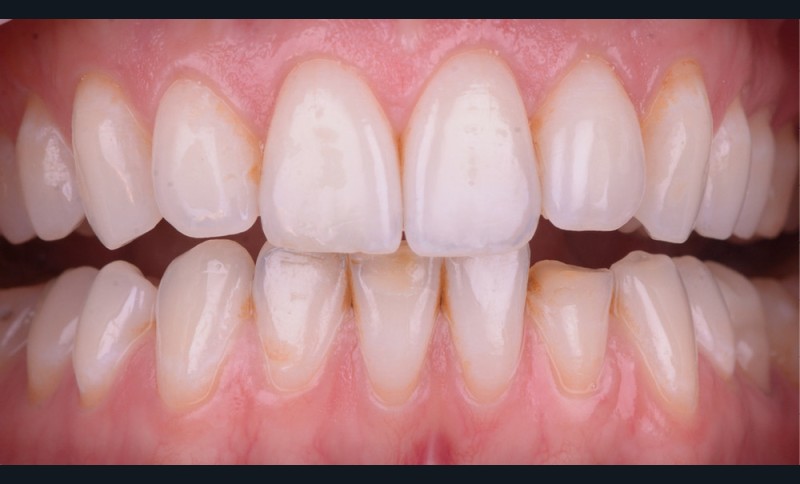

Restaurations adhésives directes

Il existe aujourd’hui sur le marché des résines composites fluides chargées, résistantes mécaniquement et qui présentent de bonnes propriétés optiques. Le choix d’une résine qui présente de bonnes propriétés optiques impose néanmoins une photopolymérisation en fine épaisseur. Ainsi, dans le cas d’une perte de substance supérieure à 2 mm, il est préférable de reconstruire la surface en plusieurs incréments [2]. L’injection de résine au travers de la clé ne concerne ainsi que la couche la plus superficielle.

Afin d’obtenir un comportement optique le plus proche possible de celui de la dent naturelle, l’auteur recommande de réaliser le corps de la dent au préalable à l’aide d’un composite de restauration plus saturé. C’est uniquement la couche la plus superficielle qui est injectée. La technique d’injection de composite nécessite le respect d’un protocole strict et comporte quelques difficultés qu’il convient d’anticiper.